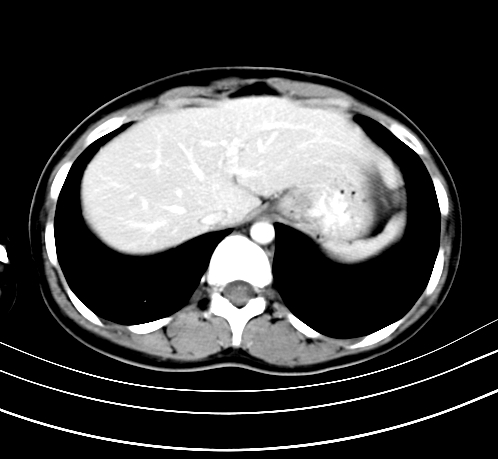

标题: CT23915:女 20岁 全身长疙瘩三年 今日多体位查 看看吧 [打印本页]

标题: CT23915:女 20岁 全身长疙瘩三年 今日多体位查 看看吧

动脉期

神经纤维瘤病

支持神经纤维瘤。